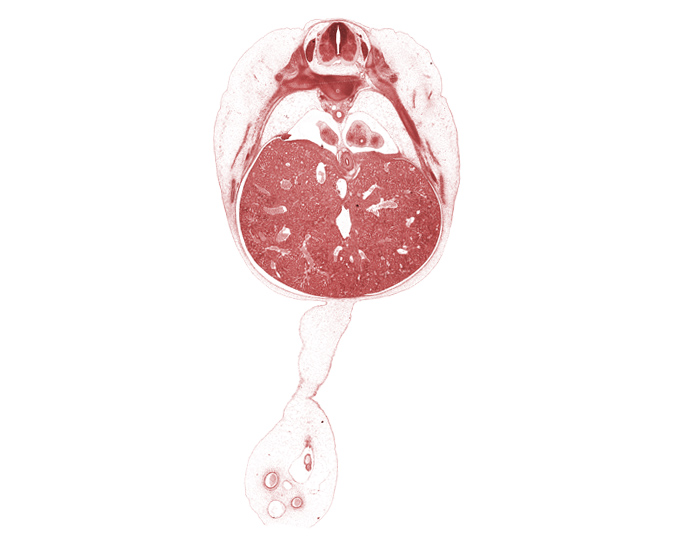

Carnegie Embryo #4430   |   Location: 21-17

Keywords: T-8 / T-9 intervertebral disc, T-8 intercostal nerve, T-8 spinal ganglion, allantois, dorsal meso-esophagus, ductus venosus, esophageal hiatus in diaphragm, left lobe of liver, left umbilical artery, lower lobe of left lung, lower lobe of right lung, muscular part of diaphragm, omphalomesenteric artery, pleuroperitoneal opening, rib 10, rib 9, right lobe of liver, right umbilical artery, umbilical coelom, umbilical cord, umbilical vein

Source: The Virtual Human Embryo.